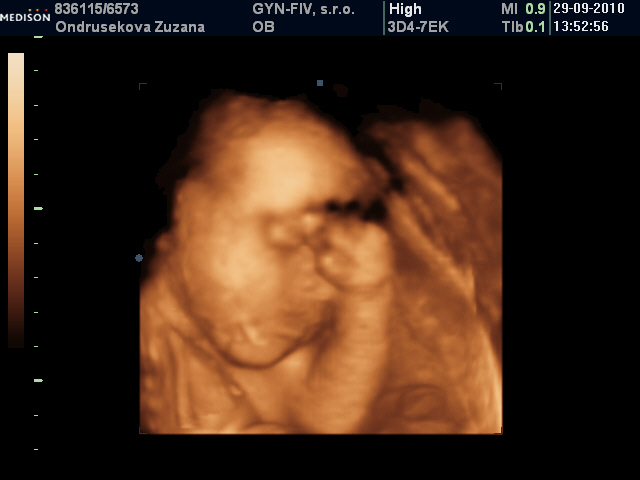

♥70 dní do porodu♥holčička má 1430 g a je hlavičkou dolů♥